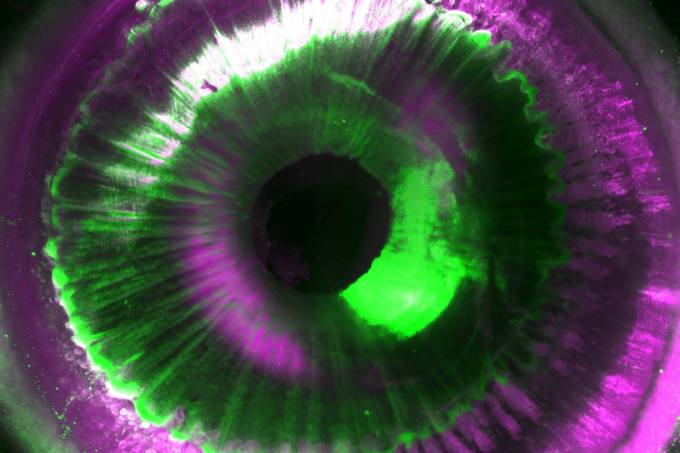

O produto, que foi chamado de Ultramiscrocope Blaze, foi constituído de algoritmos de deep learning, que é um aprendizado de máquina feito a partir de várias camadas. Com o microscópio e a limpeza do órgão que, juntos, receberam o nome de tecnologia Shanel, os cientistas conseguiram tornar órgãos humanos de doadores transparentes.

(Helmholtz Zentrum München/Ertürk lab/Reprodução)

Ali Ertürk, diretor do Instituto de Engenharia de Tecidos e Medicina Regenerativa da Helmholtz Zentrum München e autor do estudo, diz acreditar que a Shanel pode se tornar indispensável: “A tecnologia pode se transformar em algo essencial para mapear órgãos humanos intactos em um futuro próximo. Isso aceleraria dramaticamente nossa compreensão de órgãos como o cérebro, seu desenvolvimento e função na saúde e na doença”, disse Ertürk, em nota.